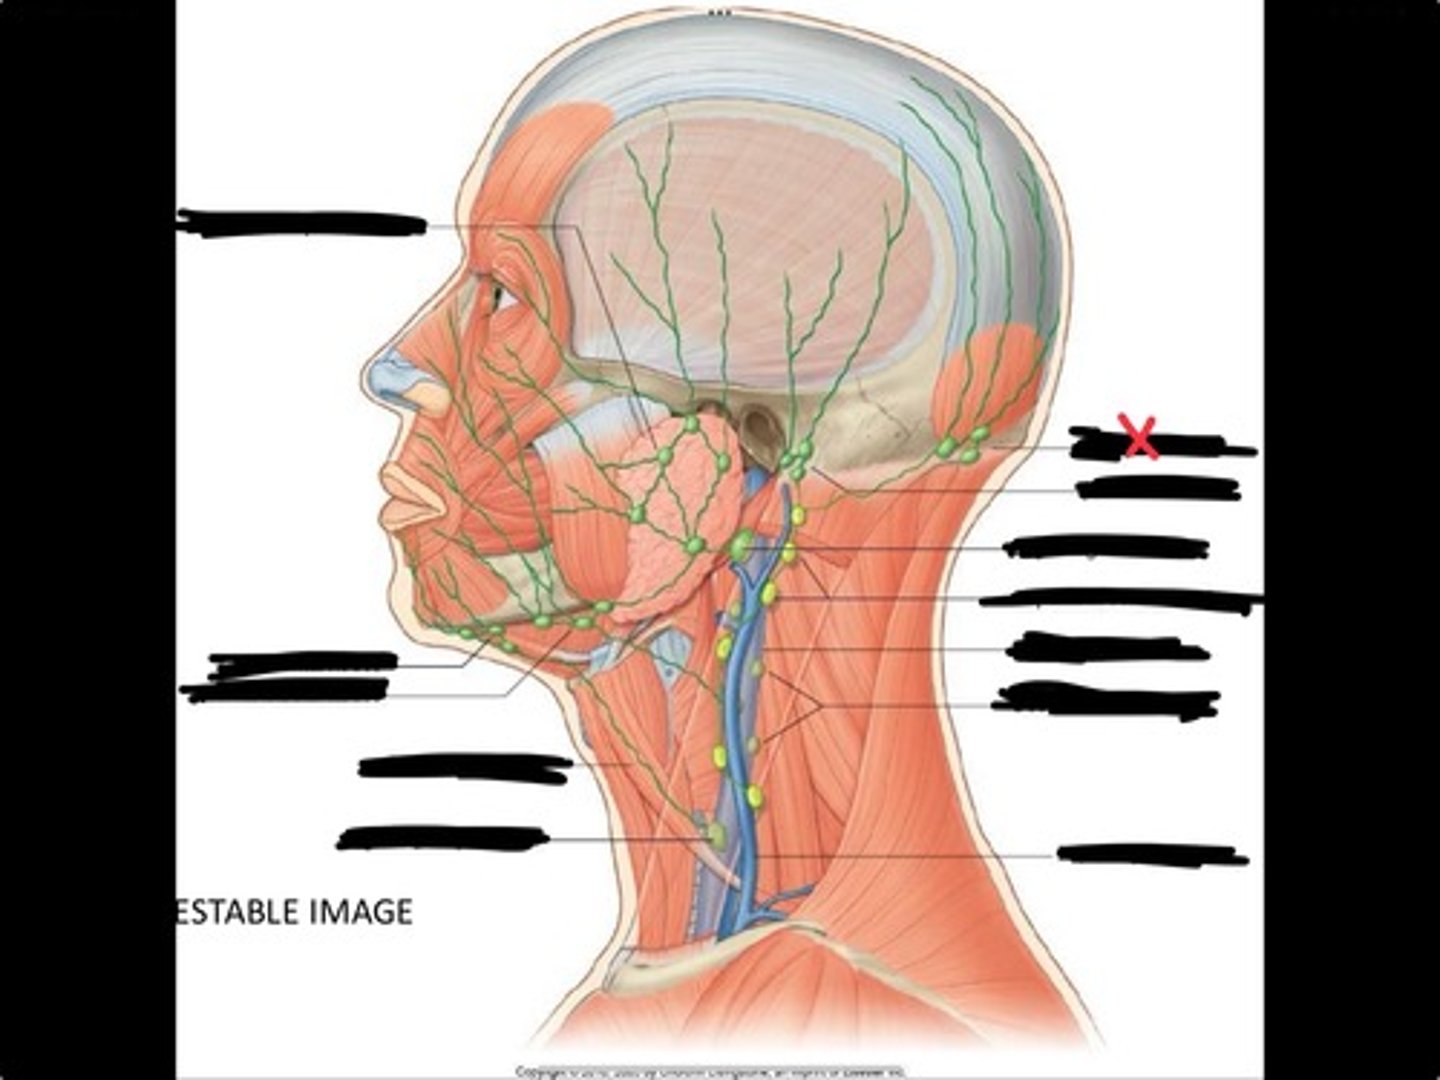

Jugulo-omohyoid node

Omohyoid muscle

Submandibular nodes

Submental nodes

Pre-articular/parotid nodes

Occipital nodes

Mastoid nodes

Jugulodigastric nodes

Superficial cervical nodes

Internal jugular vein

Deep cervical nodes

External jugular vein